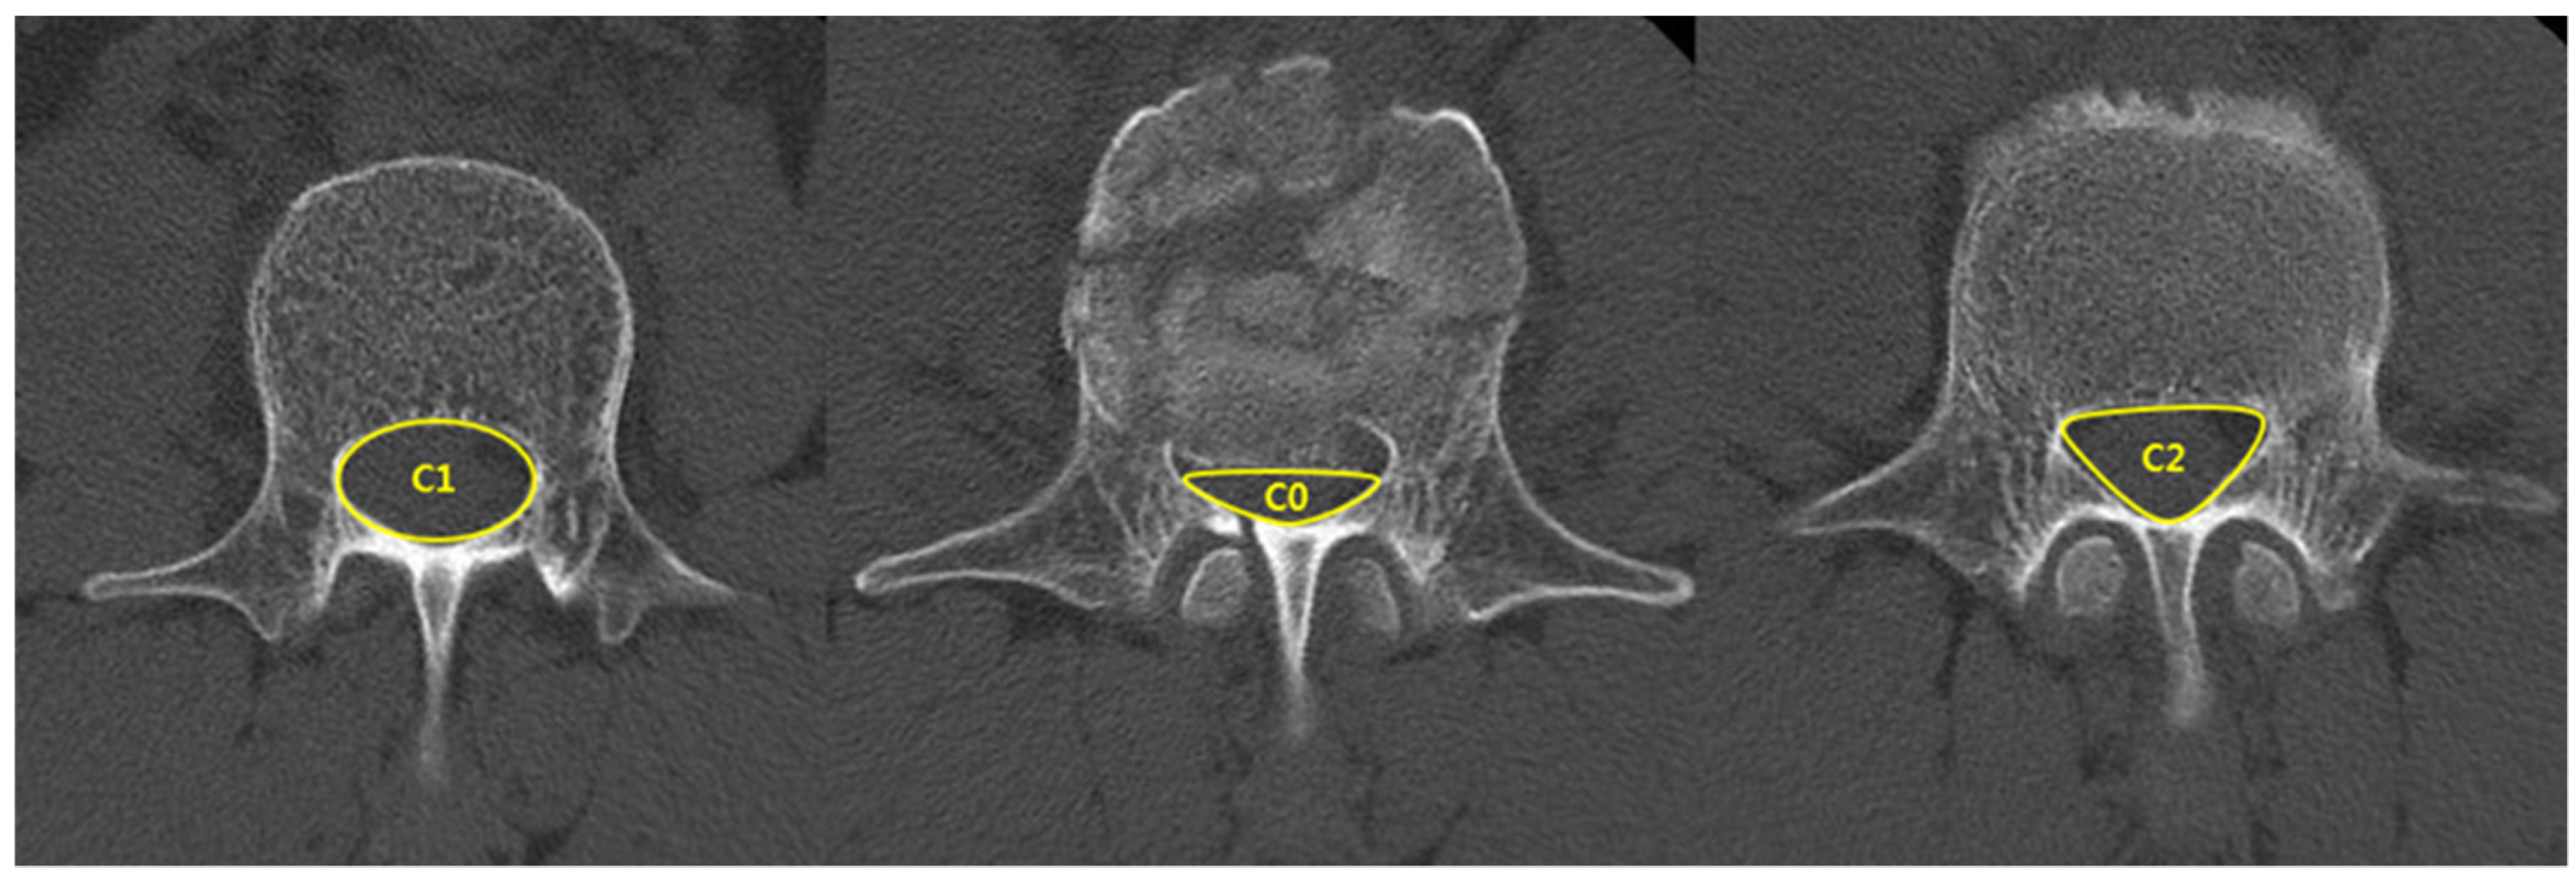

| Spinal canal compromise (%) ‡ | 27.9 ± 7.6 | 35.7 ± 13.3 | 0.03 |